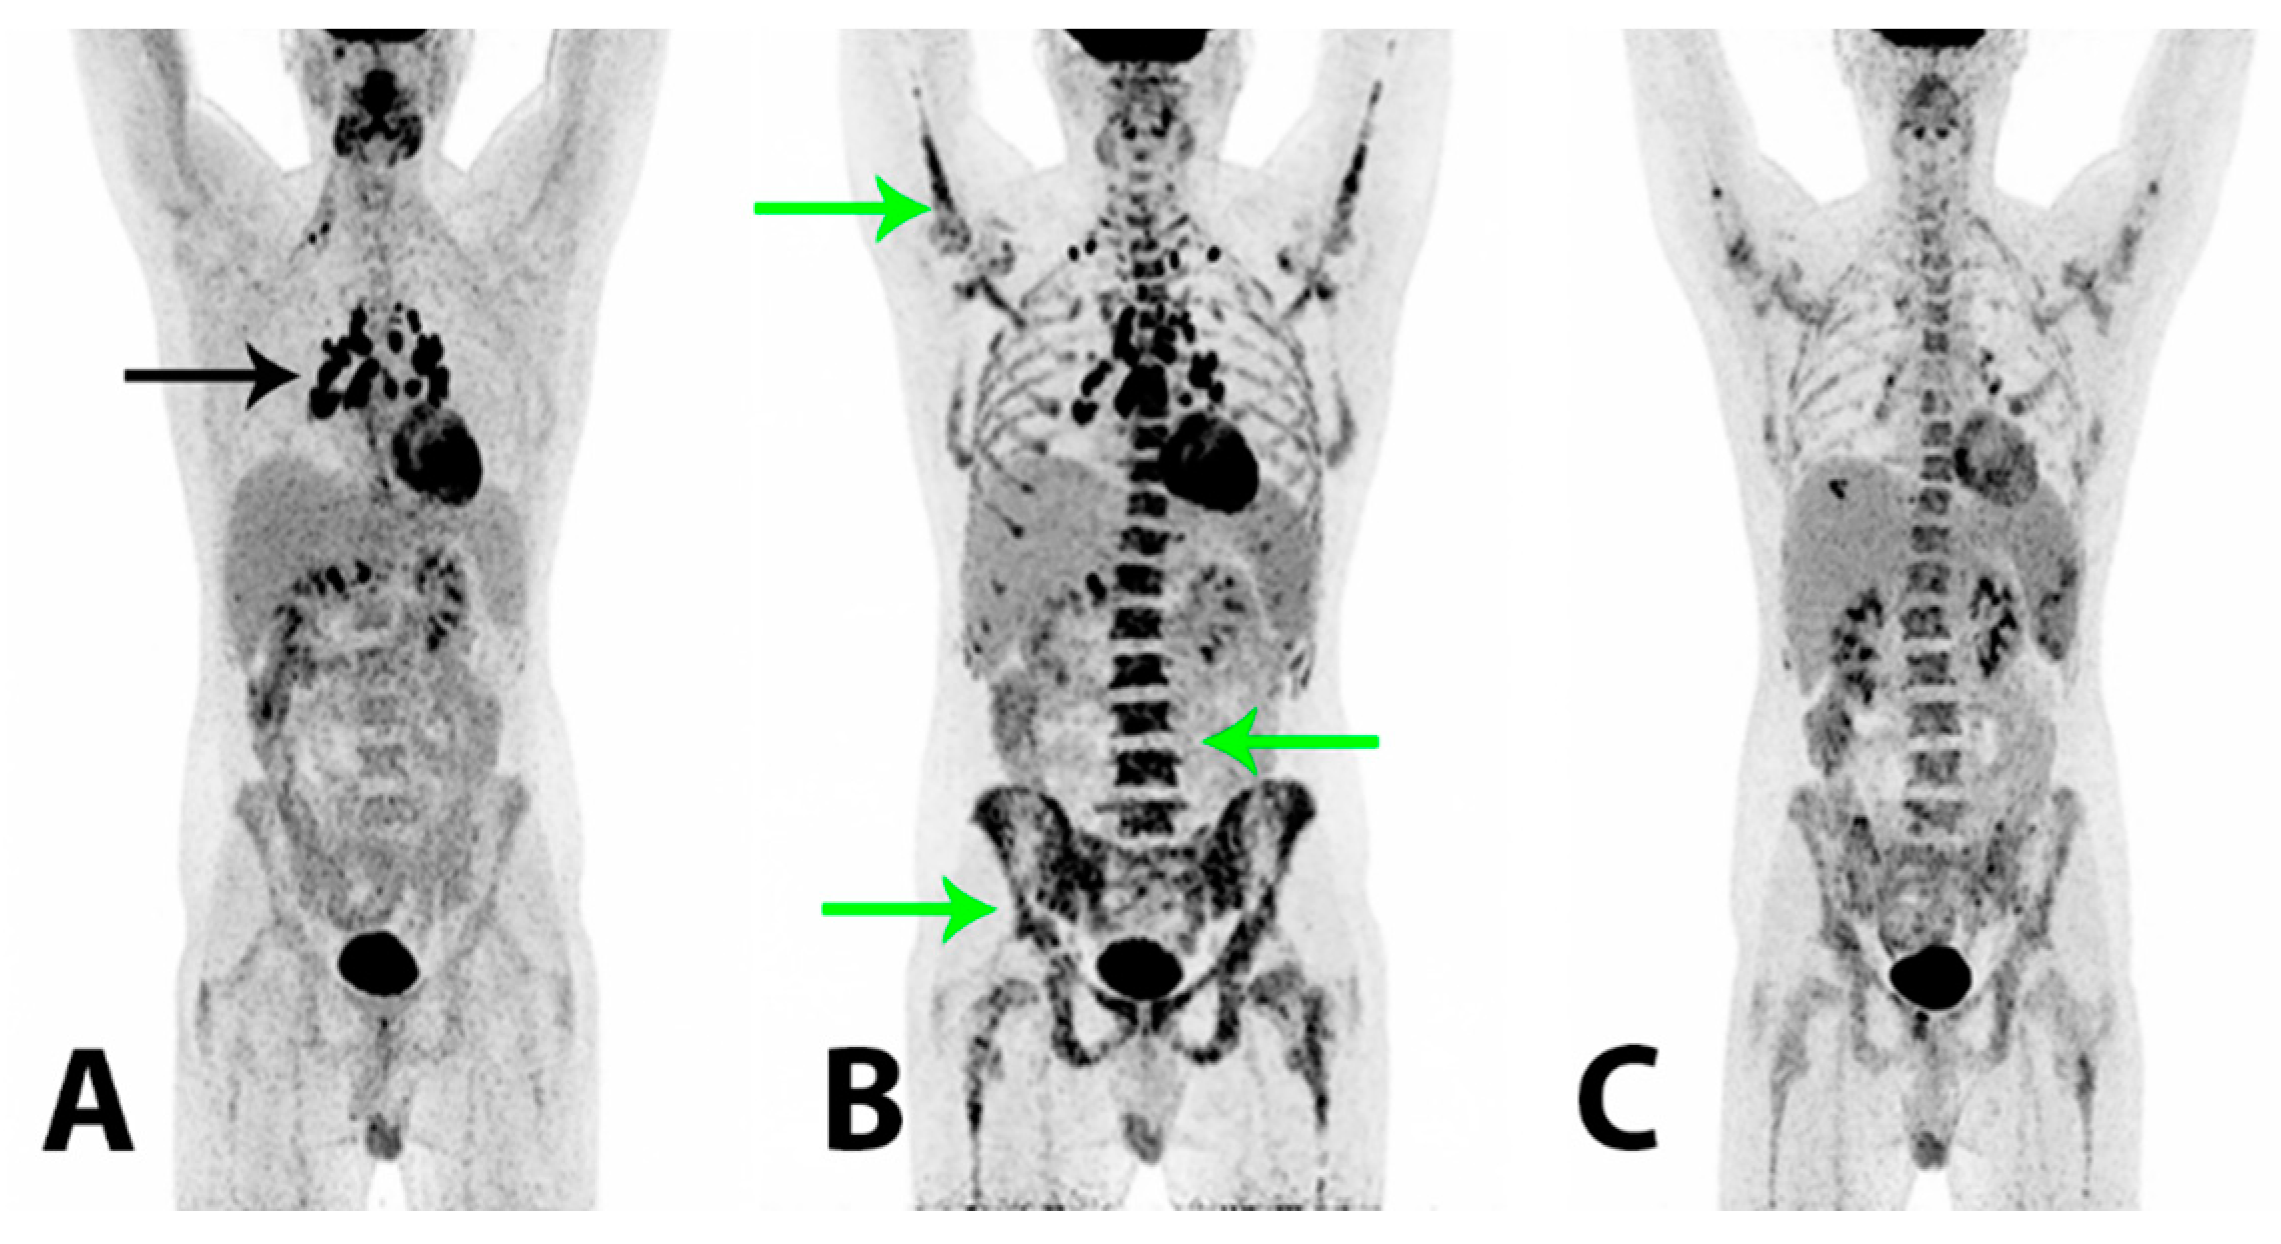

To reduce the risk of HS relapse, an experimental therapeutic approach with high-dose chemotherapy administering a BEAM (carmustine + etoposide + cytarabine + melphalan) regimen and a subsequent autologous stem cell transplant (SCT) was initiated. The patient tolerated the treatment well and at follow-up +60 days after BEAM/SCT the regeneration of bone marrow was considered complete and the tumor marker plasma LDH was still within the reference range (157 U/L). 2-[18F]FDG PET/CT (A) demonstrated a metabolic CR and a further morphological PR. There were now relatively symmetrically localized, metabolically active lymph nodes at the right root of the neck, in both sides of the mediastinum and the lung hilum (black arrow), compatible with possible granulomatous inflammation. Two months later the patient reported a gradual worsening of bone pain in the lumbar and pelvic region. The plasma LDH was now elevated (450 U/L) and thrombocyte and hemoglobin levels were low. A relapse of HS was suspected, which was confirmed by a bone marrow biopsy that showed a massive infiltration of almost 100% of malignant histiocytic cells with blastoid morphology and an immunohistochemical profile similar to previous specimens. Findings on 2-[18F]FDG PET/CT (B) were compatible with a relapse, demonstrating a heterogeneous, pathologically increased FDG-uptake in the bone marrow in the axial and peripheral skeleton (green arrows). There were metabolically active lymph nodes above and now also below the diaphragm. A malignant bone marrow infiltration with a myeloid expansion was considered the cause of the patient’s bone pain. The plasma LDH rose rapidly to 5100 U/L and salvage therapy with an acute myelogenous leukemia regime (CLAG-M; cladribine + cytarabine + mitoxantrone) was initiated. The treatment had a good effect on the patient’s bone pain and wellbeing. The plasma LDH was normalized within days and histopathological examinations showed no tumor cells in the blood and no malignant cells in the bone marrow biopsy. 2-[18F]FDG PET/CT (C) demonstrated a metabolic PR of previously malignant findings in the bone marrow. There were now splenic lesions compatible with abscesses. A second course of CLAG-M was administered and, as the patient had achieved a second CR confirmed by a bone marrow biopsy, a non-myeloablative allogeneic SCT was considered. However, within a short period of time the patient again reported bone pain and he developed cutaneous papules on the trunk end lower extremity from which a biopsy showed HS. The plasma LDH also increased rapidly and 2-[18F]FDG PET/CT (not shown) again demonstrated progression with a pathologically increased FDG-uptake in the bone marrow and new metabolically active cutaneous lesions on the abdomen. The findings were compatible with a systemic relapse and an allogeneic SCT was now not a feasible treatment option. Palliative treatment with a modified FLAG-Ida regime (fludarabine + cytarabine + idarubicin + filgrastim) initially had a good effect on the bone pain; the cutaneous lesions regressed and the plasma LDH decreased. However, the effect was short-lived and the patient experienced intermittent fever, bone pain, fatigue and blood cell counts that demonstrated cytopenia. The plasma LDH again increased. The patient’s clinical condition worsened significantly and after short periods of treatment with high-dose cytarabine and hydroxycarbamide, further treatment attempts with intensive regimen chemotherapy were considered futile. No appropriate protocolled treatment was found suitable for the patient and the treatment aim of long term survival was abated. The patient passed away shortly after, 15 months after his initial hospitalization.